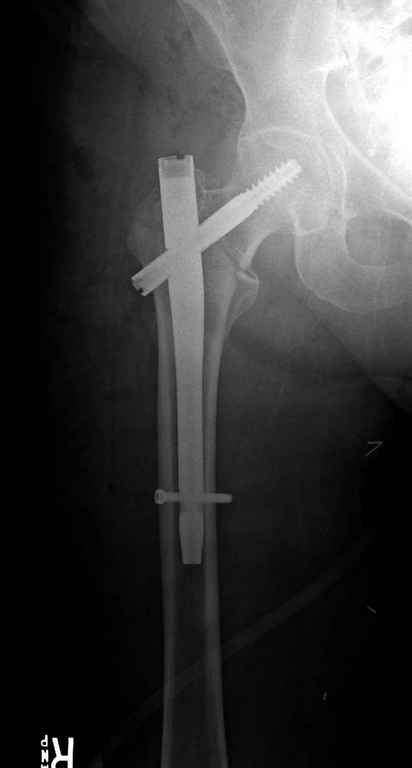

С приходом менее агрессивных блокируемых цефаломедуллярных гвоздей (Gamma 3 и другие) изменилась тактика лечения. Несмотря на то, что вся стабильность держится вокруг одного блокирующего винта, в большинстве случаев гвозди приводили к успеху.

Вашему вниманию представляется похожий случай, пациентке 70, осложнился в течение одного месяца после операции. Ревизия с заменой сустава, кабельная фиксация на трохантер. При установке в дистальном диафизе обнаружен тонкий кортикальный слой и сделана профилактика от возможного перелома аллографтом.